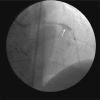

Figure 2.

Figure 2.. Heavily calcified left anterior descending artery (arrows) with entrapped burr at distal.